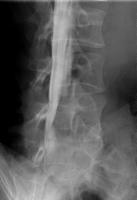

全脊椎撮影

脊椎全体の配列を観察する検査です。

自然位で寝た状態から、体を左右に曲げた側屈位や、腕と脚を引っ張った伸展矯正位、背中を反らせた最大後屈位などを撮影します。

EOS検査の立位荷重位と比較することが可能です。